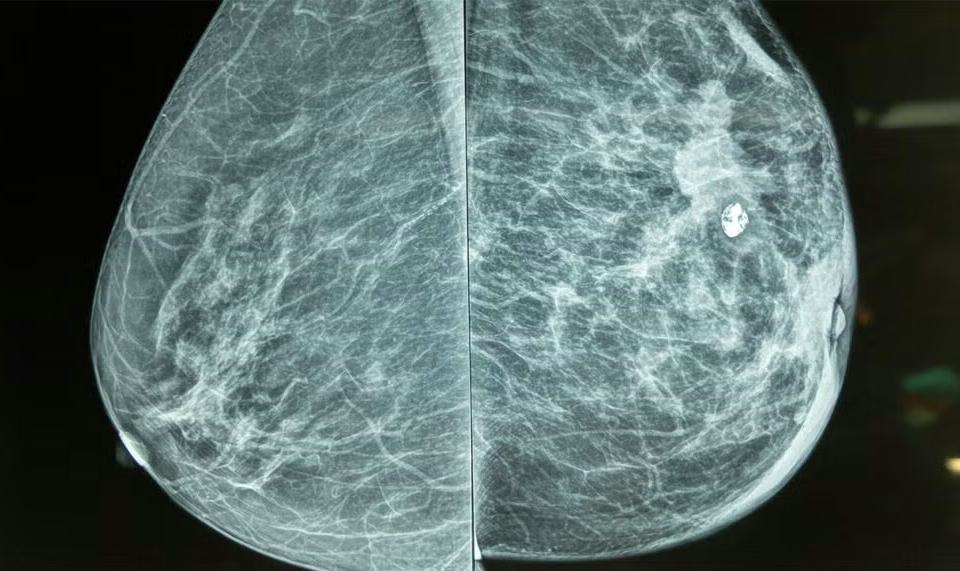

Stage 1 breast cancer is the earliest invasive stage of breast cancer, meaning the cancer cells have spread beyond the ducts or lobules into nearby breast tissue but remain small in size. Typically, tumors in this stage measure up to 2 centimeters and have not spread to lymph nodes or distant organs. A stage 1 breast cancer mammogram often shows small lumps, calcifications, or abnormal tissue structures, which may not be felt during a physical exam.

At this stage, breast cancer is highly treatable, with survival rates significantly higher than in later stages. Detecting it through mammography helps ensure timely intervention before the cancer progresses.

Mammograms often assist doctors in distinguishing between these types, guiding treatment decisions.

Often, a stage 1 breast cancer mammogram detects abnormalities long before symptoms appear.

Mammography is the gold standard for detecting stage 1 breast cancer, helping doctors decide on the next diagnostic steps.